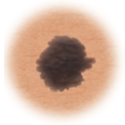

Melanoma

Skin cancer showing asymmetry.

Asymmetry

When half of the mole does not match the other half